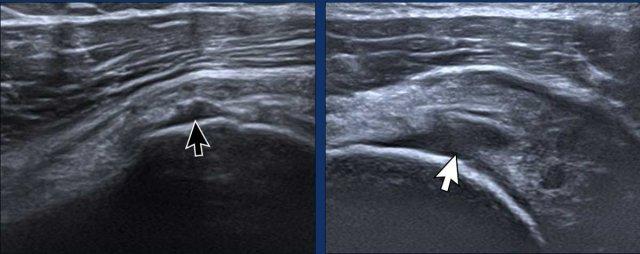

Partial thickness tears

Here two examples of a partial tear on the articular side.